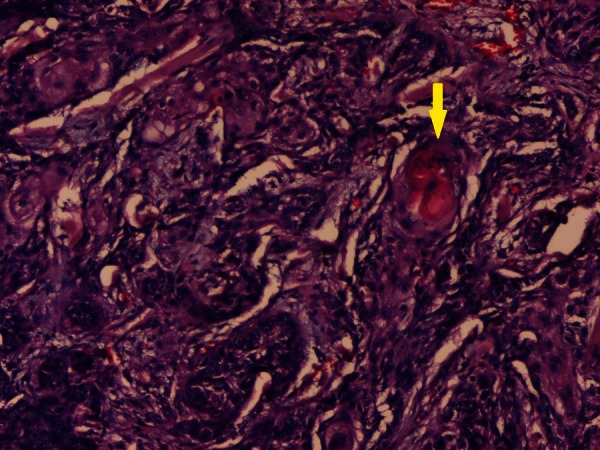

Figure 4.

Microphotograph of tissue section showing malignant squamous cells arranged in nests and sheets inside a desmoplastic stroma. Foci of keratin pearl formation is seen (yellow arrow) (H&E, ×100).